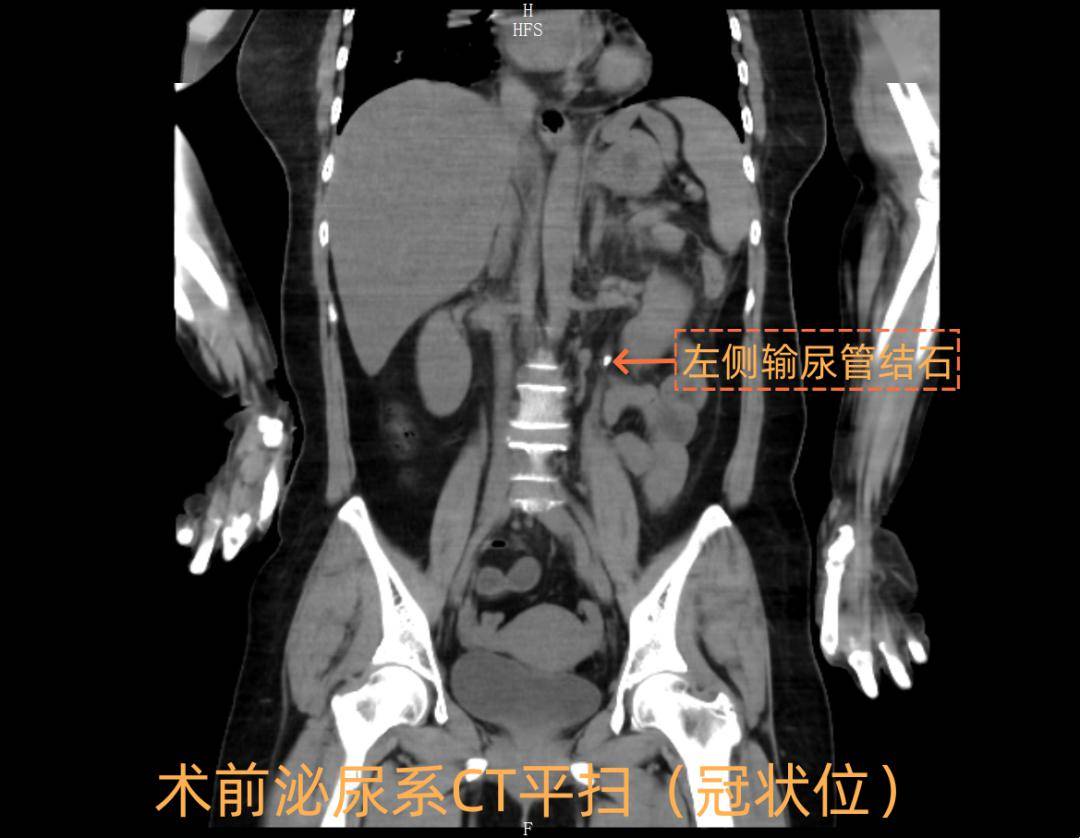

中西医协同攻克重症91 | 与"死神"赛跑!